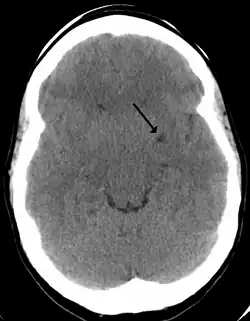

Son una estructuras fisiológicas en el parénquima cerebral normal.[2] Consisten en espacios perivasculares que rodean a las arterias perforantes del cerebro, y se debe pensar siempre en ellos al visualizar estructuras quísticas en la sustancia blanca del cerebro y ganglios basales, redondeadas o alargadas, siguiendo el trayecto de los vasos perforantes.[5]Se pueden observar a través de una resonancia magnética cerebral.[5] Allí las características morfológicas de imagen de los espacios de Virchow-Robin son áreas redondas o tubulares, de bordes suaves.[2]

En ocasiones pueden crecer y convertirse en gigantes espacios de Virchow-Robin.[4]Al agrandarse y convertirse en espacios gigantes de Virchow-Robin producen un efecto de masa que puede traer diversos síntomas neurológicos.[1]En casos anormales se relacionan con diversas patologías neurológicas neurodegenerativas, como la enfermedad de Alzheimer, las enfermedades cerebrovasculares y las lesiones cerebrales traumáticas,[2]ictus, esclerosis múltiple, angiopatía amiloidea cerebral,[6] e hidrocefalia.[3]Incluso se ha descrito un caso de neuralgia del trigémino secundaria a los espacios de Virchow-Robin gigantes en el área dorsal pontino.[1]